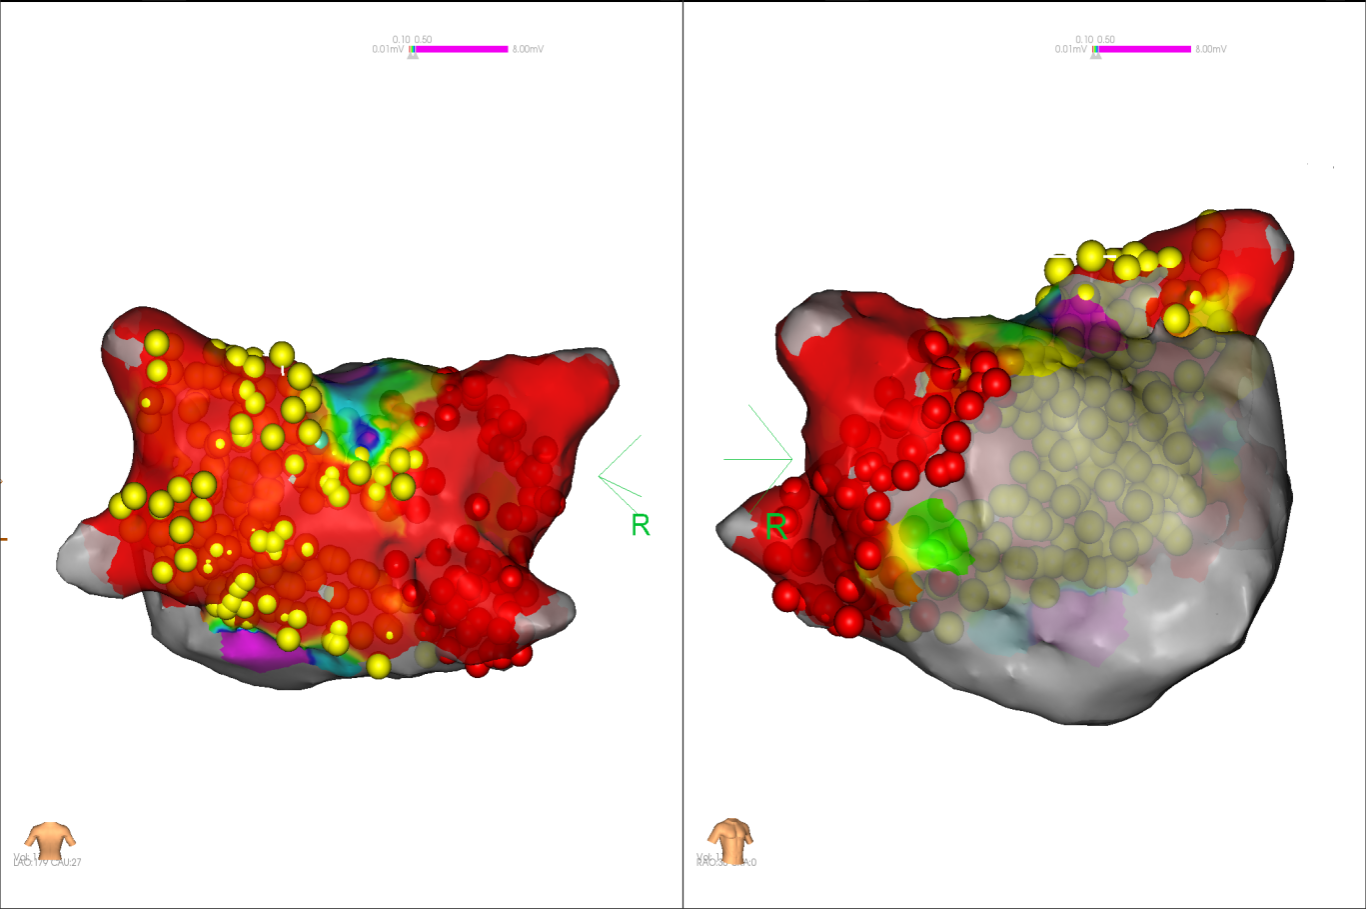

经充分术前评估及准备后,该患者手术在抗心衰药物持续静脉泵入、高流量吸氧支持下及麻醉、护理团队的通力配合下进行,由薛建颖、崔明亮主治医师具体实施。术中通过右侧股静脉送入心腔内超声至右心房,排除左房血栓后成功指导房间隔穿刺,沿可调弯鞘管送入锦江心脏脉冲电场消融导管至左房,构建左房三维解剖模型并行基质标测,标测显示左房基质差,分别行左侧、右侧肺静脉及后壁BOX消融。消融参数:1800v,400ms,400μs,共放电消融140次(消融右肺静脉时转复为窦性心律),验证双肺静脉均隔离。术后重新标测显示所有肺静脉均已急性阻滞,消融效果理想,肺静脉前庭损伤范围也达到了预期的标准,同时心腔内超声监测未见明显心包积液。手术仅用时30分钟,时间明显缩短,手术过程精准高效。术后患者恢复情况良好,维持窦性心律。

图2 术中电压标测提示左房基质差

图4 消融前后基质标测提示肺静脉消融效果明显